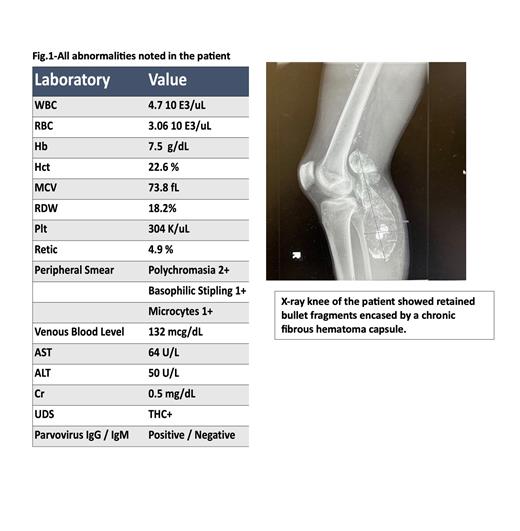

A 19-year-old Hispanic male presented to the emergency department with symptoms of worsening abdominal pain, anorexia, weight loss (10 lbs. over 2 months), constipation, low back pain, right knee pain, and headache that has been going on for two weeks. Complete blood counts showed microcytic anemia with a peripheral smear showing basophilic stippling; Computerized tomography of the head, abdomen, and pelvis showed no acute findings. Iron profile was within normal limits. Upon careful history and examination, he revealed that he had suffered an accidental gunshot injury to his right knee 6 years ago with retained bullet and had undergone a popliteal artery repair. His knee ray showed retained bullet fragment encased in a chronic calcified hematoma. This led us to suspect lead poisoning and ordering of venous lead level. His blood lead level came back and was elevated to a toxic level of 136.2 mcg/dl (Normal <5.0 mcg/dl).